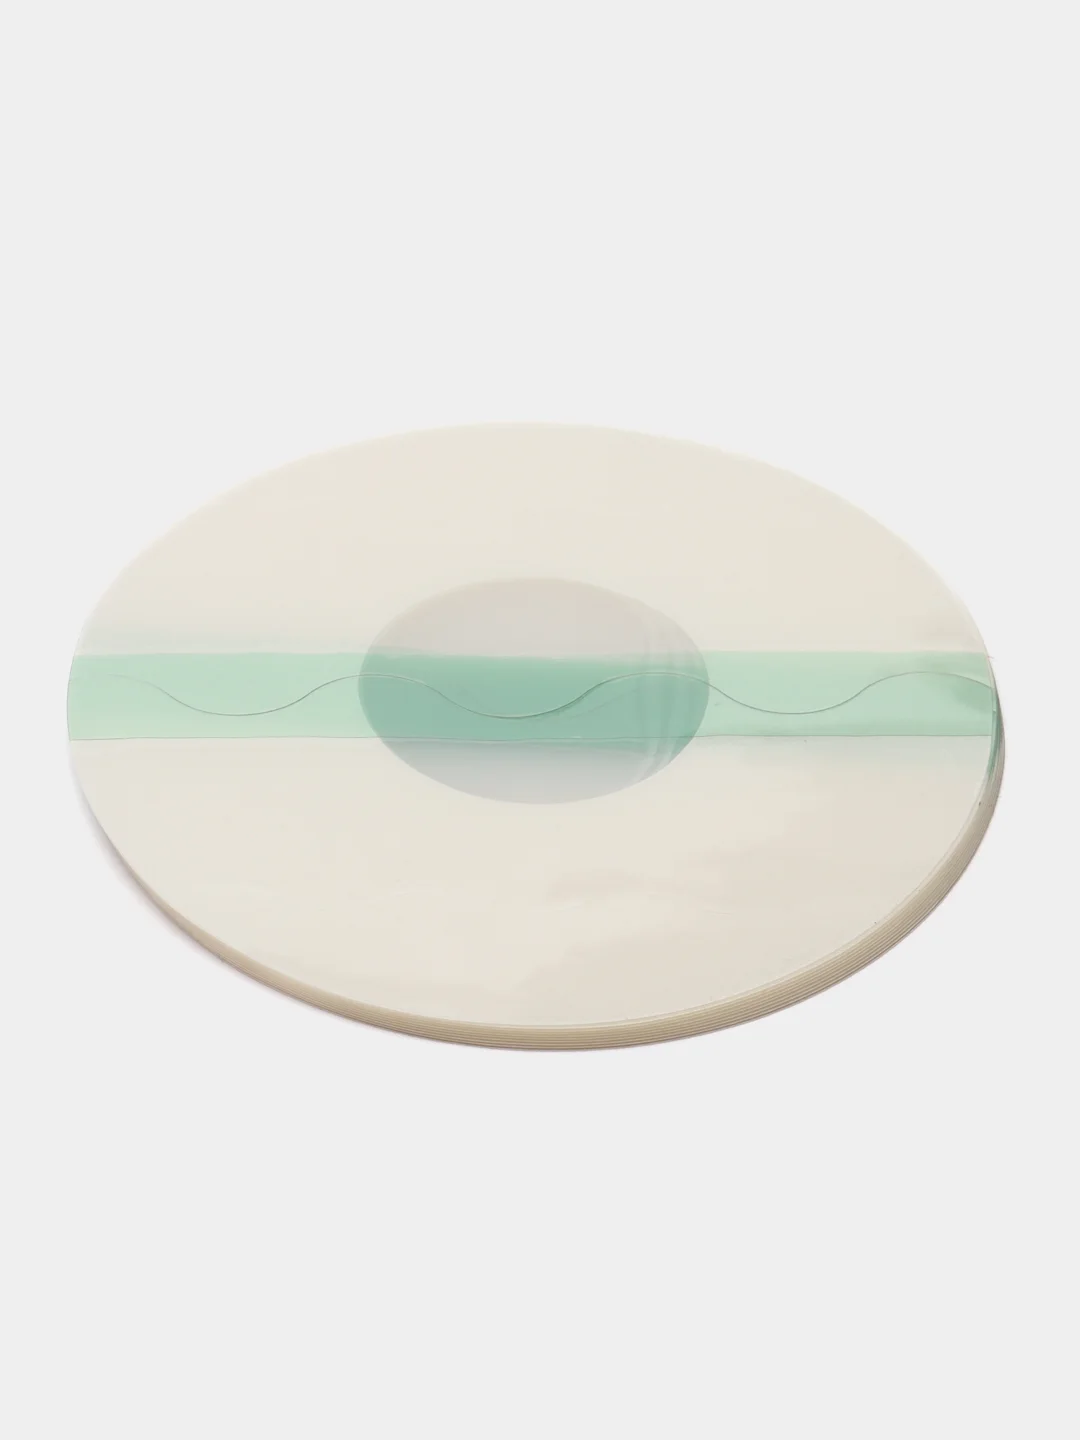

в наборе 10 шт

круглые диаметр 7 см

овальный 8,5 см на 10 см